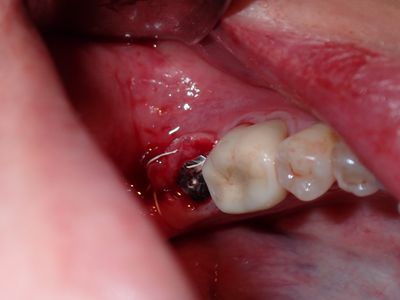

relatively straightforward implant placement but very soft bone. placed 4.8mm implant after 3.5mm drill, Initial implant was stable (30Ncm) but after changing healing abutment, got loose, removed, placed longer implant (4.8 X 10mm) not stable, placed 5.5X10 tissue level, stable.